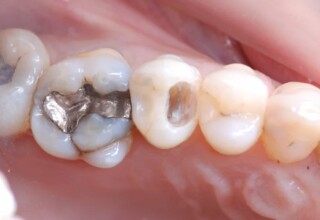

Posterior Tooth Root Canal Restoration with a Composite Resin Filling

The common restoration of a posterior tooth after a root canal is a crown. Its main purpose is to protect from fracture and concomitant extraction. In very few cases that specific criteria (mainly remaining tooth structure) are met or where finances predominate, an extensive composite filling can restore both aesthetics and function.

Restoration of a cracked molar with composite resin

Cracked teeth present a challenge in restorative dentistry both from the aspect of complexity of the restoration itself (usually large filings) and the necessary providings to avoid a complete fracture. The presented case demonstrates the simplest approach of a bonded direct restoration with composite resin. It is based on the principle of an adhesive filling that “holds” the remaining tooth structures “together”. The restored molar remained healthy for two years, then required a root canal and a crown was placed for maximum protection.